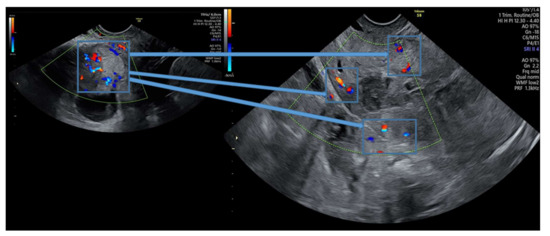

| Patient No | Peak bHCG Value | Gestational Age | CSP | Treatment Course | Outcome |

|---|---|---|---|---|---|

| P1 * | 99,999 | 7w + 1d | Type 1 | 1. Intramuscular methotrexate injection 2. Uterine artery embolization 3. Suction evacuation | No complications |

| P2 | 99,999 | 5w + 2d | Type 2 | 1. Intramuscular methotrexate injection 2. Uterine artery embolization 3. Suction evacuation | No complications |

| P3 | 62,309 | 7w + 2d | Type 2 | 1. Intramuscular methotrexate injection 2. Uterine artery embolization 3. Suction evacuation | No complications |

| P4 | 5938 | 5w + 5d | Type 1 | 1.Intramuscular methotrexate injection 2. Suction evacuation | No complications |

| P5 | 4579 | 5w + 6d | Type 2 | 1.Intramuscular methotrexate injection 2. Uterine artery embolization 3.Suction evacuation | No complications |

| P6 | 70,373 | 6w + 5d | Type 1 | 1. Intramuscular methotrexate injection 2. Uterine artery embolization 3. Suction evacuation | No complications |

| P7 | 46,317 | 6w + 2d | Type 2 | 1. Intramuscular methotrexate injection 2. Uterine artery embolization 3. Suction evacuation | No complications |

| Patient No | Residual Myometrium Thickness (mm) | Fetal Heartbeat | Vascularization | Crown-Rump Length (mm) | Gestational Sac Diameter (mm) | BMI |

|---|---|---|---|---|---|---|

| P1 * | 2 | absent | increased | 11 | 22/20 | 27.5 |

| P2 | 2.1 | absent | increased | Not measured | 11 | 22.5 |

| P3 | 1.6 | present | increased | 13 | 24 | 28.4 |

| P4 | 3.3 | absent | normal | 2 | 8 | 33.6 |

| P5 | 4 | absent | normal | Not measured | 8 | 29.4 |

| P6 | 3.8 | absent | increased | 4 | 23 | 19.7 |

| P7 | 3.5 | present | increased | 5 | 28 | 21 |